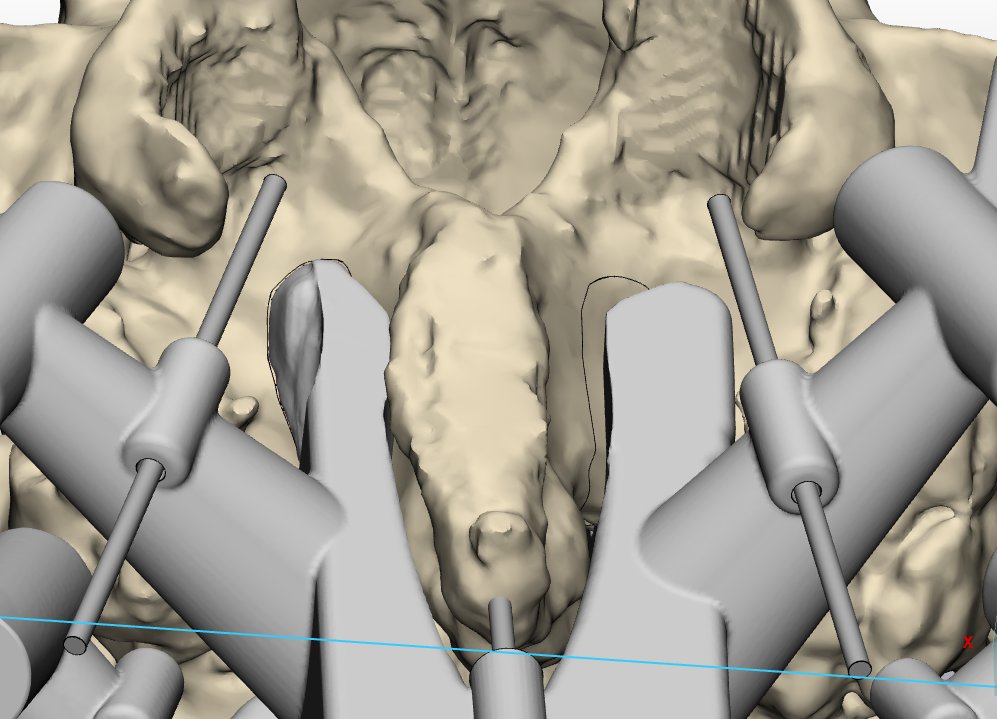

@icsebre 🔊 Èric Barreda: “El model de disseny de peces 3D fa una rèplica exacta de l’anatomia del pacient per poder simular la intervenció quirúrgica que se li realitzarà, prevenint possibles complicacions"

@icsebre 🔎 Aquest model de medicina personalitzada, gràcies a la tecnologia 3D, permet als professionals sanitaris crear pròtesis úniques per a cada pacient, adaptades a les seves necessitats i anatomia, millorant la qualitat de vida.